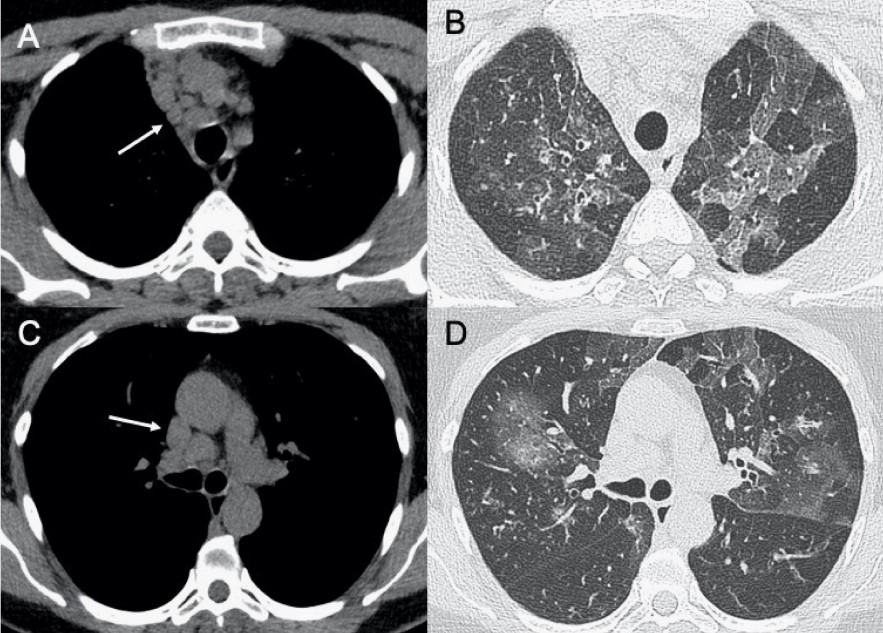

?巨細胞病毒

● CXR:彌漫性和雙側實變伴間質受累。

● CT:間質和肺泡浸潤,雙側和不對稱性GGO區域,與實質實變區域相關。

圖8 巨細胞病毒性肺炎。圖(A–C)顯示其輕度實質受累的情況。圖(D、E)顯示患者有彌漫性GGO和鋪路石征,胸片(F)中同樣可見。

?EB病毒

● CXR:淋巴結腫大,雙肺間質實質受累。

● CT:淋巴結腫大和較少見的間質浸潤伴彌漫性GGO和實變。

圖9 EB病毒性肺炎。圖(A,C)顯示縱隔淋巴結腫大(箭頭),與雙肺局灶性小葉GGO相關(B,D)。